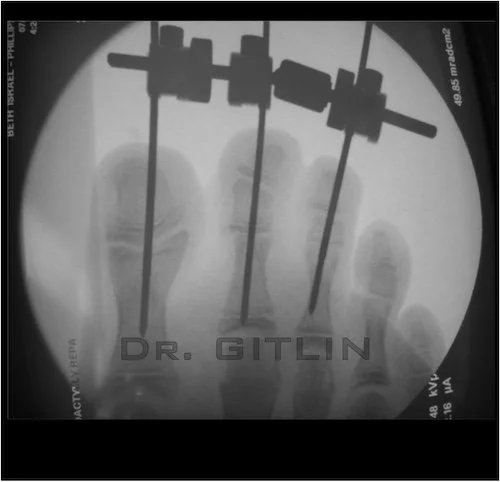

We applied an external fixator to the patients toes and use stretched them apart over a period of 2 weeks. This allows skin to actually regenerate!! We the were able to bring the patient back to surgery with the toes all fanned away from each other and simply cut between the toes and sew it all up.

X-ray of a foot with four nails inserted through bones, labeled with the text 'DR. GITLIN'.